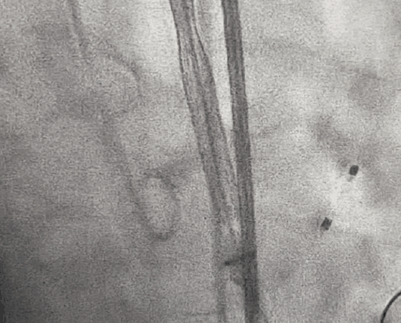

手术过程概览:

术前右冠造影

主动脉根部造影提示瓦氏窦整体形态较大,无冠瓣瓣叶钙化斑块程度较重。

导丝跨瓣

TaurusOne®轻松过弓

TaurusOne®释放过程:

瓣膜展开后与术前策略讨论的风险预期相符,受无冠瓣较重钙化和瓣上结构整体的影响,瓣膜释放后的腰部形态受限,决定使用25mm球囊后扩治疗。

最终瓣膜形态和位置良好,造影无明显瓣周漏和返流。